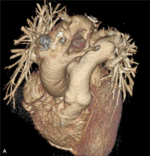

RYCINA. Badanie wykonane 64-rzędowym tomografem komputerowym jednolampowym. Akcja serca podczas badania – 87 uderzeń/min.

Zakres badania – cała klatka piersiowa. [A] Rekonstrukcja VR uwidoczniła prawostronny łuk aorty. [B] Warstwa poprzeczna na poziomie łuku aorty. Widoczne są: niepełny pierścień naczyniowy otaczający tchawicę i przełyk utworzony przez łuk aorty i tętnicę podobojczykową lewą otaczającą tchawicę i przełyk (strzałki). Ściana tętnicy podobojczykowej zawiera blaszki miażdżycowe zwężające jej światło 40%. [C] Warstwa poprzeczna na poziomie nadnercza lewego – widoczny guzek nadnercza lewego (strzałka). [D] Rekonstrukcja VR uwidoczniła prawostronny łuk aorty z częściowym pierścieniem naczyniowym.

- prawostronny łuk aorty (rycina A),

- brak pnia ramienno-głowowego z izolowanym odejściem tętnicy podobojczykowej prawej i tętnicy szyjnej wspólnej,

- zwężenie 40% tętnicy podobojczykowej lewej w odcinku proksymalnym za jej odejściem od łuku aorty; tętnica otaczająca tchawicę wzdłuż jej przedniej ściany tworzyła wraz z prawostronnym łukiem aorty niepełny „pierścień” (rycina B),